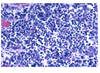

What kind of lung cancer is this?

Squamous cell carcinoma

C for Squamous cell - (bc the curve of the q looks like a c)

Central, Cavitary, Calcium, Keratin

What kind of lung cancer is this?

Small cell lung cancer

S for Small cell - smokers, central, small blue cells, syndromes, agressive

Neuroendocrine cells are small and blue